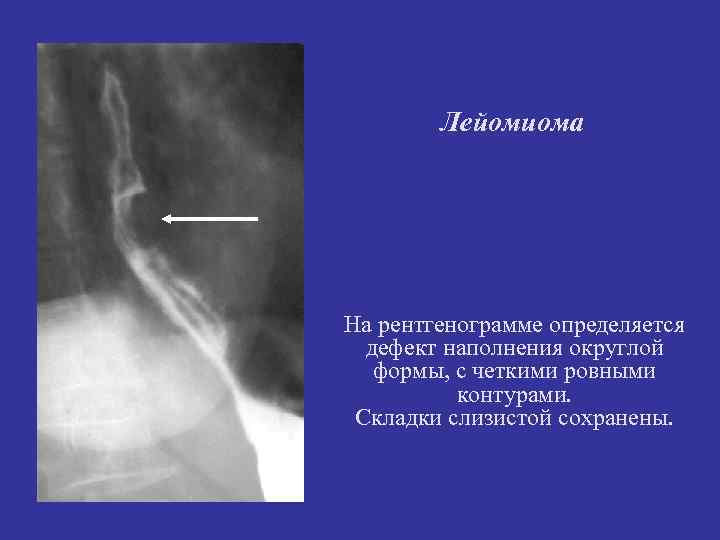

Лейомиома На рентгенограмме определяется дефект наполнения округлой формы, с четкими ровными контурами. Складки слизистой сохранены.